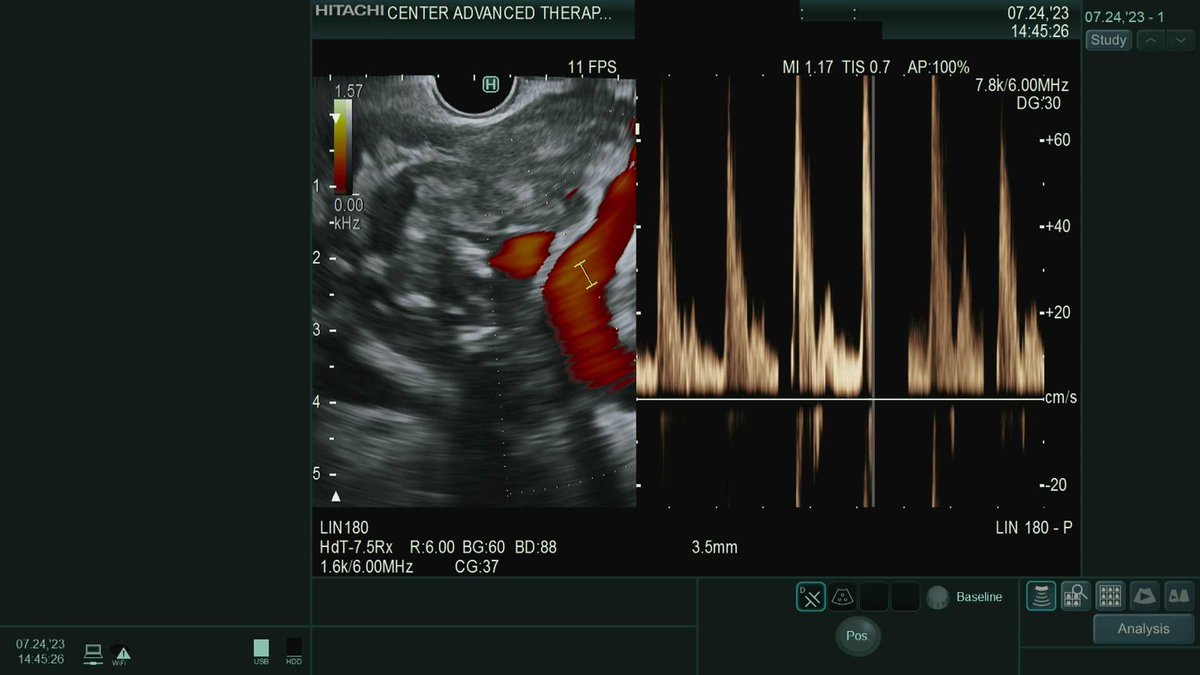

During an eval for a cystgastrostomy for a large WON, we saw this vessel running right through it. Likely the splenic artery. #GITwitter #pancreas

English